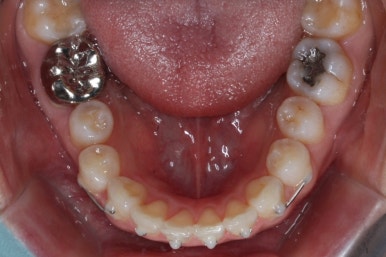

부산앞니교정 키다리아저씨치과에 처음 내원하셔쓸 당시의 입안 모습입니다.

앞니가 살짝 삐뚤어진 것을 볼 수 있고, 삐뚤어진 사이에서 약간의 틈새도 있었습니다.

예전에 치료 받으셨던 앞니 부분에 약간의 변색도 와서 미적으로 좋지 못한 상황이였습니다.